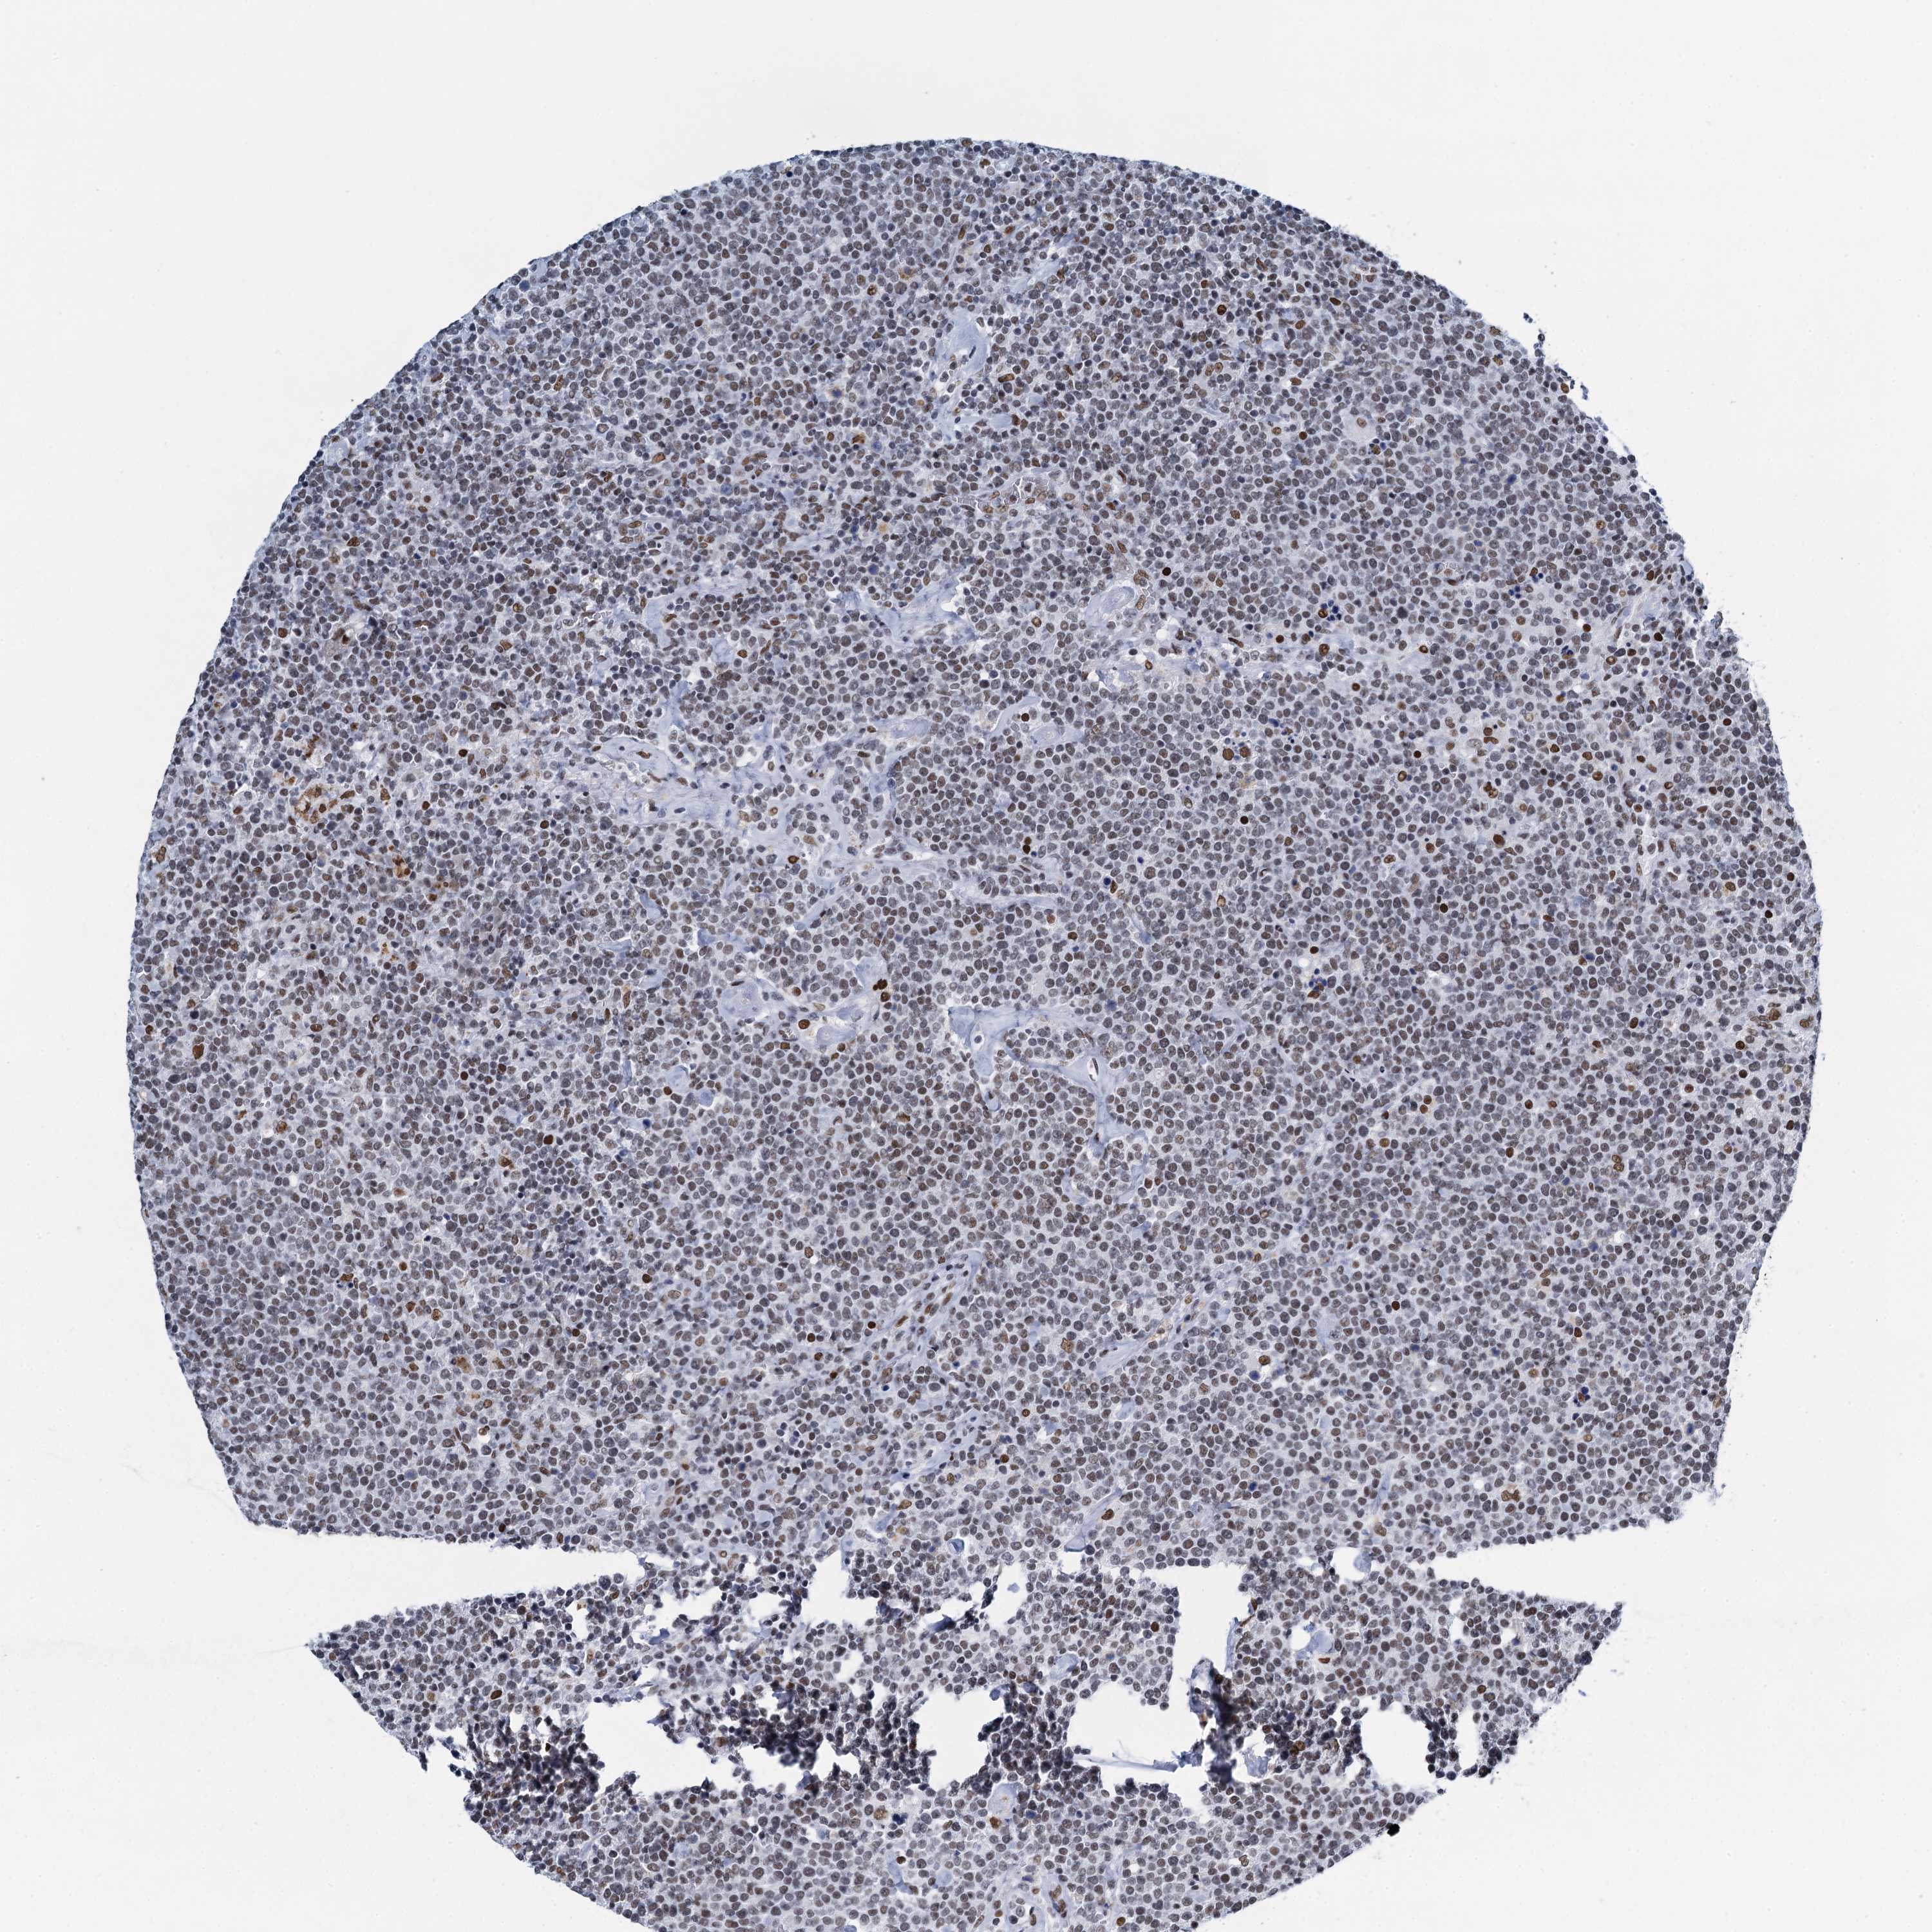

LYMPHOMA - Protein expressioni

A mouse-over function shows sample information and annotation data. Click on an image to view it in a full screen mode. Samples can be filtered based on level of antibody staining by selecting one or several of the following categories: high, medium, low and not detected. The assay and annotation is described here.

Antibody stainingi

Antibody staining in the annotated cell types in the current human tissue is reported as not detected, low, medium, or high, based on conventional immunohistochemistry profiling in selected tissues. This score is based on the combination of the staining intensity and fraction of stained cells.

Each image is clickable and will lead to virtual microscopy that enables deeper exploration of all samples and also displays staining intensity scores, fraction scores and subcellular localization as well as patient and tissue information for each sample.

Antibody HPA041632

Hodgkin's disease, NOS

Malignant lymphoma, non-Hodgkin's type, High grade

Malignant lymphoma, non-Hodgkin's type, Low grade